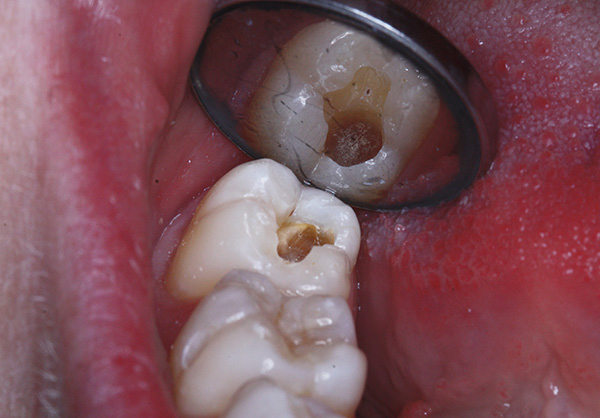

La fotografia sotto mostra un esempio di significativa distruzione cariata di un dente del giudizio: